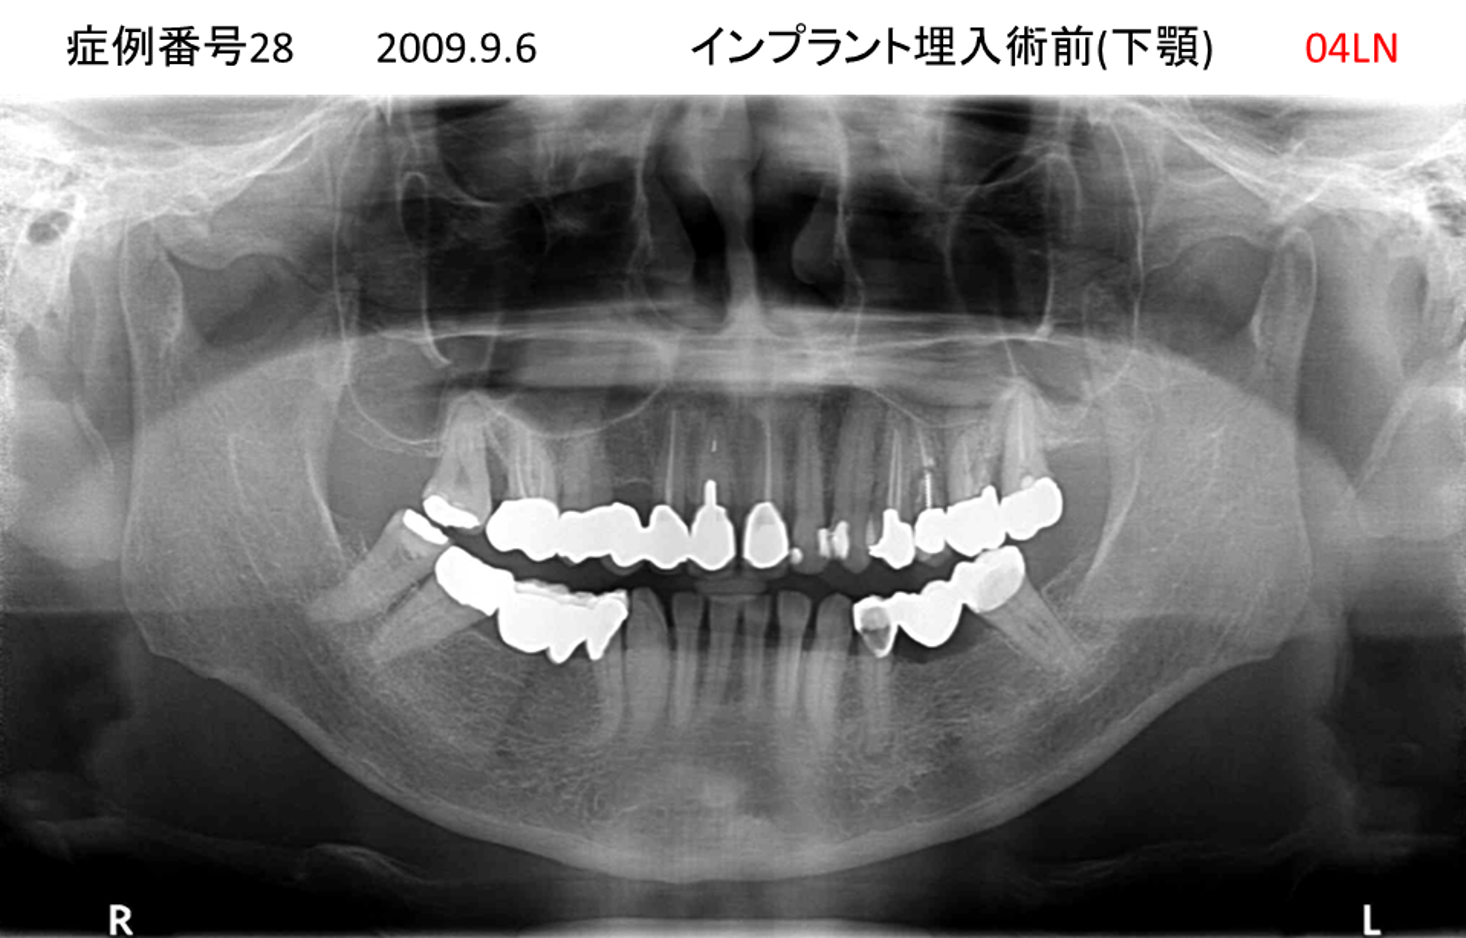

義歯が合わない、噛めない患者様のインプラント症例

| 治療名称 |

インプラントコーヌステレスコープ |

| 治療費用 |

270万円+税 |

| 治療期間 |

4か月 |

| 患者さんの症状(主訴) |

義歯が合わない、噛めない |

| 治療内容 |

インプラント、義歯作製(コーヌステレスコープ) |

| 治療結果 |

しっかり噛めるようになった。見栄えが良くなった。 |

| 治療の注意点(リスク/副作用) |

義歯が壊れた場合、インプラントが壊れた場合は再治療が必要 |